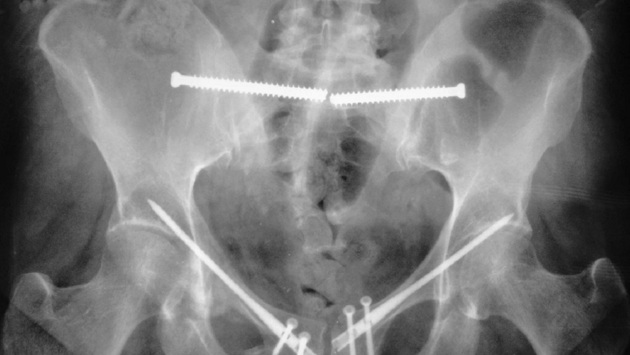

Сейчас вместо широких разрезов при остановке кровотечения используют тампонаду через небольшой разрез-прокол. При этом для анализа ситуации врачи используют методы компьютерного моделирования. Это же помогает при определении допустимых пределов нагрузки для метода фиксации.

Для подготовки к операции помогают 3D-модели костей таза. По данным innovanews.ru, после стабилизации костей таза винтами, стержнями и пластинами можно более эффективно прогнозировать восстановление пациентов.